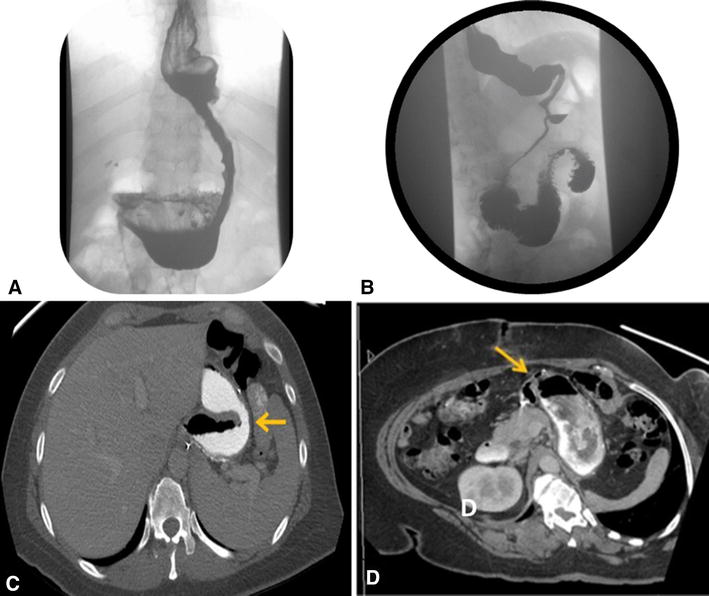

Upper GI series revealing gastric leak. Download Scientific Diagram